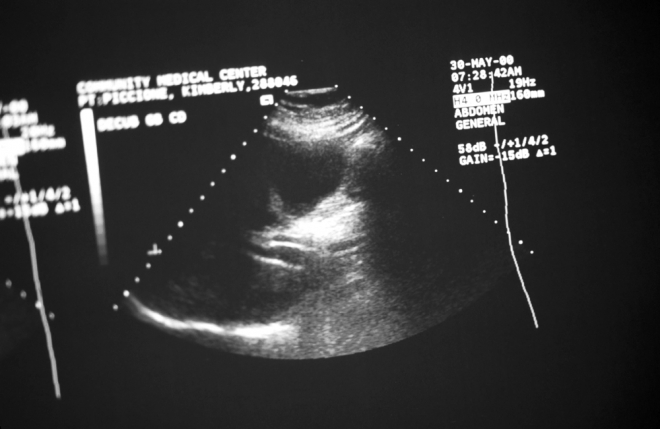

기사와 관련 없는 자료 이미지